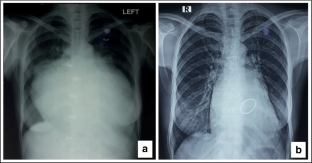

Study involved 31 patients who underwent mitral valve replacement for mitral regurgitation. Patient’s preoperative and postoperative echocardiography (conventional parameters and global longitudinal strain) and other parameters like functional status, radiological findings, and electrocardiogram were recorded to evaluate left ventricular function.

All patients presented in advanced stage with New York heart association class III (67.7%) and IV (32.3%). There was significant decline in left ventricular ejection fraction (with the mean value from 64.58 to 40.13%) and global longitudinal strain (− 15.57 ± 4.98to  8.97) in the immediate postoperative period (~ 7 days). However, there was a rise in both left ventricular ejection fraction (mean 52.48%) and in global longitudinal strain (mean − 14.44 ± 3.67) at 3 months. Left ventricular and atrial size decreased significantly immediately after surgery, which further declined at 3 months. We also found that patients who attained a left ventricular ejection fraction of > 50% in postoperative period had better left ventricular ejection fraction and global longitudinal strain preoperatively. In addition, they had smaller cardiac size and milder pulmonary hypertension comparatively.

Fig. 1